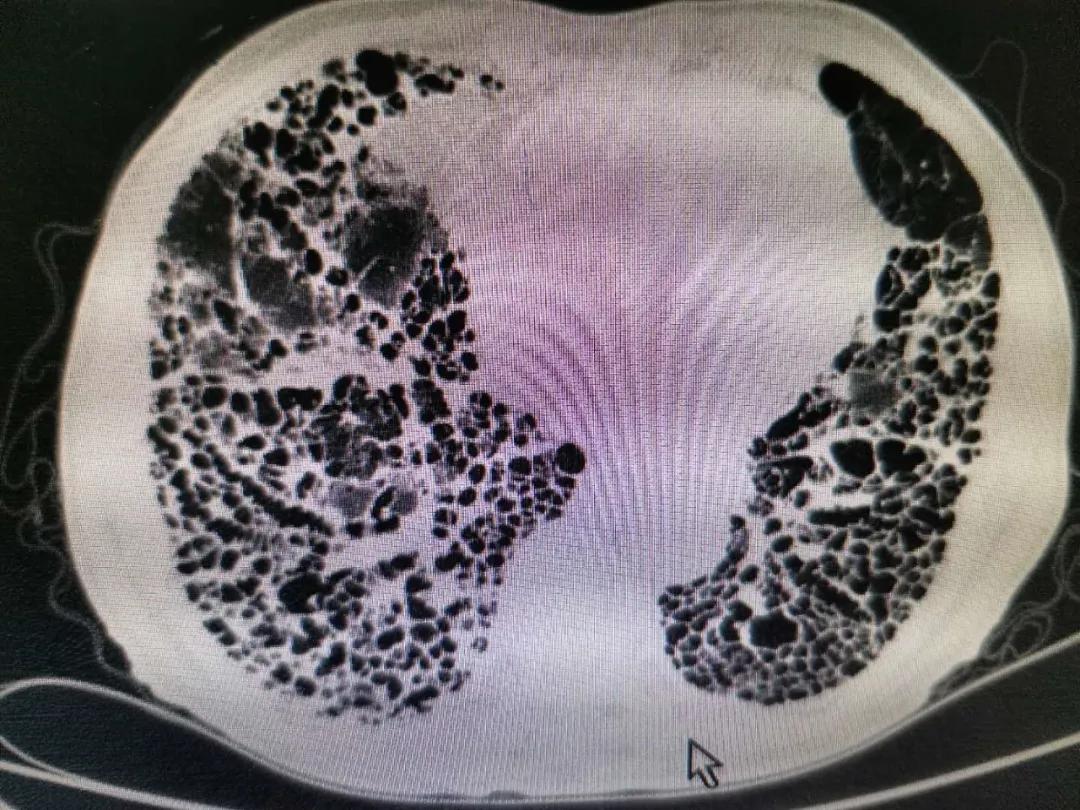

刘大爷近2年病情逐渐加重,几乎每1-2个月都需要住院治疗。今年6月下旬再次因气短加重伴发热到三院呼吸科治疗,此次病情比以往更加严重,持续高热、剧烈的咳嗽、严重呼吸困难;出现呼吸衰竭、心力衰竭、肝功能不全、低蛋白血症等多器官功能衰竭,且合并冠心病、类风湿性关节炎等多种基础疾病,病情极其危重。

刘大爷入院后,侯凤茹主任高度重视,带领整个呼吸科医疗团队立即投入紧张的抢救治疗中,通过准确地判断病情,明确诊断为特发性肺间质纤维化急性加重合并严重的肺部感染。侯主任积极组织科内研究讨论病情,充分认识到该患的肺感染存在耐药的铜绿假单胞菌和真菌的多重感染,同时存在因严重的缺氧导致的多脏器衰竭。刘大爷病情重危,命悬一线﹍﹍。